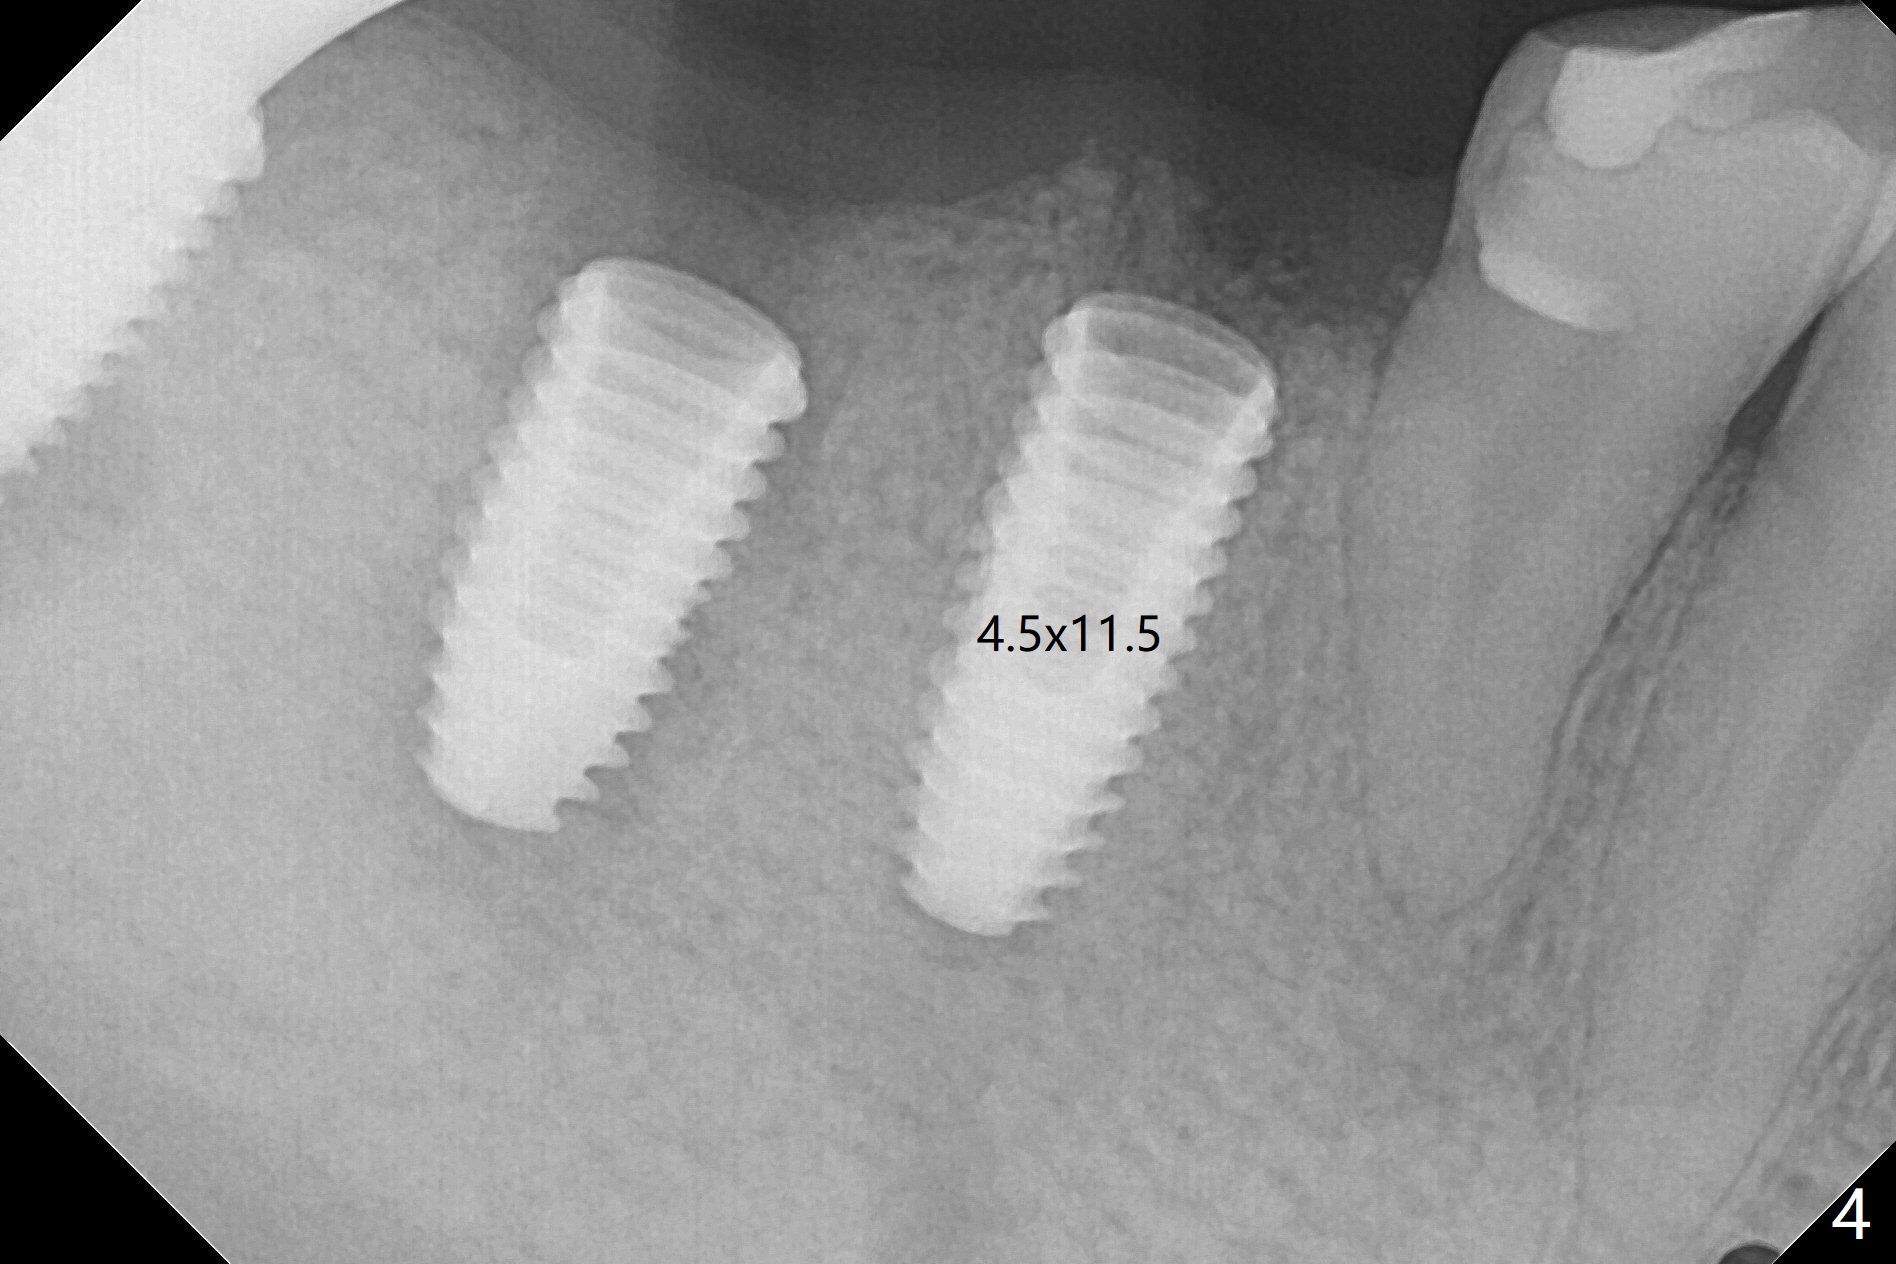

Infiltration anesthesia for guided surgery of delayed implant is effective. For a single or 2 nearby implants, one carpule is sufficient (Fig.1). More importantly hemostasis is achieved with the anesthetic injected into the crest earlier (Fig.2). Hemostasis allows the surgeon to determine easily whether tissue punch has done its job (Fig.3), even with the guide in place. With a nonstop fixture mount at #30 (Fig.1), a 4.5x11.5 mm implant is precisely placed at #29 (Fig.4). In fact this patient is nervous. More anesthetics have to be added intraop with the guide removed.